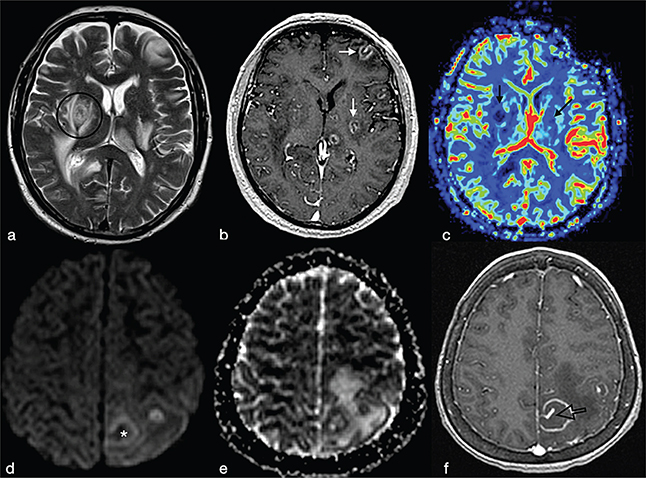

Cerebral toxoplasmosis is typical of immunocompromised patients. MRI shows multiple lesions in different stages of evolution typically located in the subcortical and periventricular white matter, in the basal ganglia and thalami. In particular, two signs are recognised as typical of toxoplasmosis: the “concentric” target sign (concentric alternating hypointense and hyperintense rims in T2w images), and the “eccentric” target sign (peripheral rim of enhancement and focal lateral eccentric enhancing nodule on T1w post-contrast) (Figure 16). On DWI, the centre of the toxoplasma abscess is seen to have ADC values higher than in pyogenic abscesses.22

FIG 16. Multiple Toxoplasma gondii Abscesses in a 45-Year-Old Immunocompromised Woman. T2w (a), T1+Gd (b, f), rCBV map (c), DWI (d) and ADC map (e). Multiple supratentorial brain abscesses in various stages of development with enhancing asymmetric nodules after Gd-injection (“eccentric target sign”) (arrows) can be observed (b, f). Note also the concentric alternating zones of hypo- and hyperintensities on T2w: “concentric target sign” (circle in a). Toxoplasma gondii abscesses typically do not show a core of restricted diffusion on DWI (asterisk in d) while low ADC values may be seen in the capsule (e).